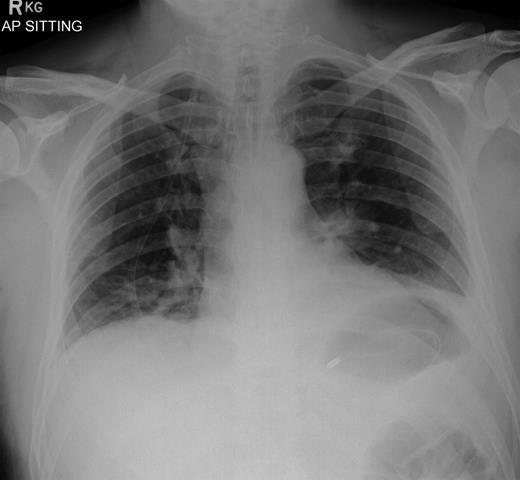

Over a year later, the same gentlemen presented to the surgical admissions unit once again with a history of acute abdominal pain. The duration and nature of symptoms were very similar to his previous admission. He again underwent plain film abdomen and erect chest radiographs that showed a large volume of free air under the diaphragm (Figs. 4 and 5).